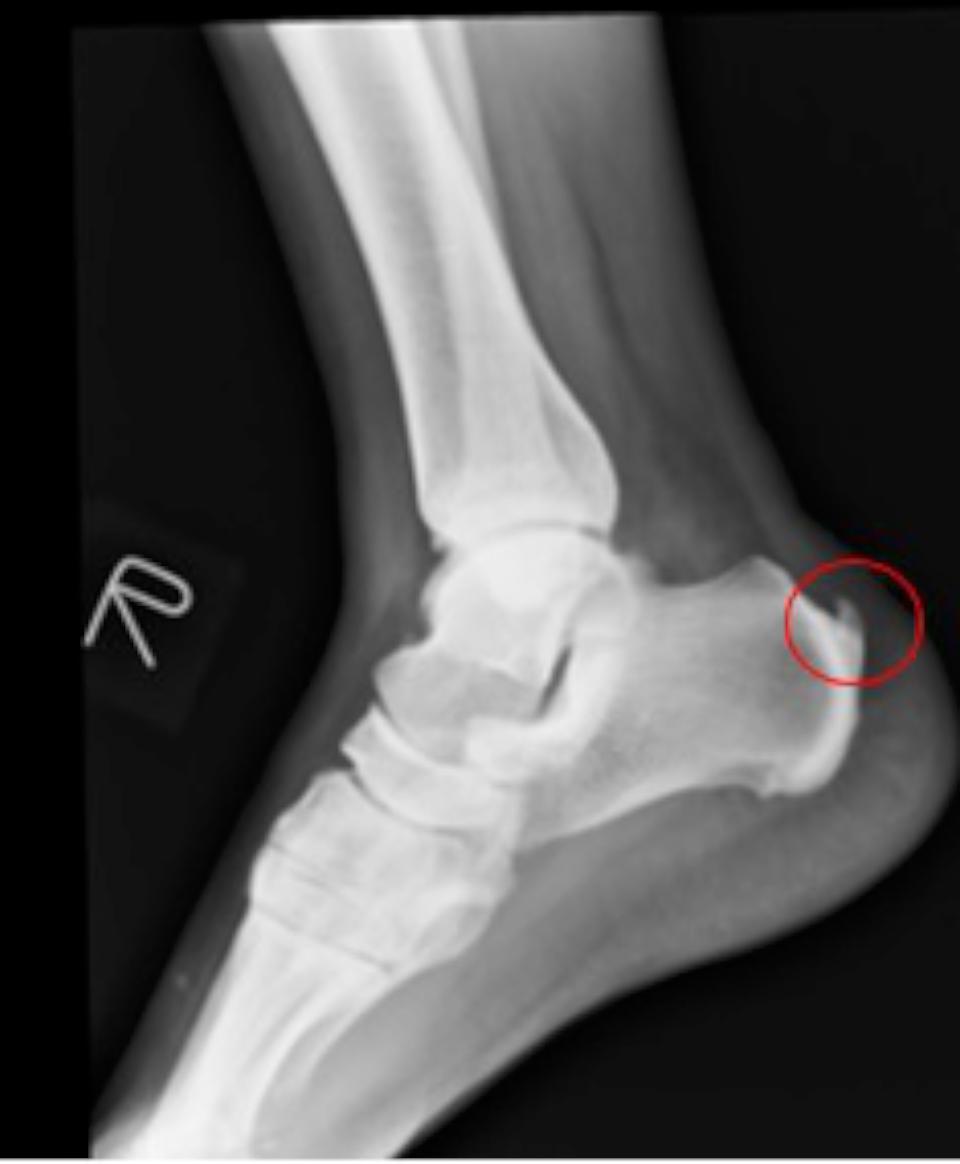

高市劉姓員警退休後陪伴高齡母親,種植竹筍過程突感足底疼痛,就醫治療兩年未見改善,經友人轉介七賢脊椎外科醫院骨關節科主任吳宗哲確診足跟骨骨刺,肇因阿基里斯肌腱過度拉扯,術後恢復正常生活。

吳宗哲說,跟骨骨刺可能出現疼痛、灼熱、腫脹等症狀,久站、運動傷害、肥胖、扁平足、高足弓等是好發族群,提醒足跟疼痛持續逾一週,建議就醫檢查治療。圖/七賢脊椎骨科醫院提供、文/高培德